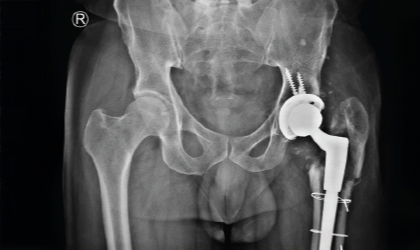

Joint Replacement Case Study

Cancer, Hips, Triumph

This is one of the youngest girls I have done a hip replacement in. Her right hip was replaced at the age of 13,